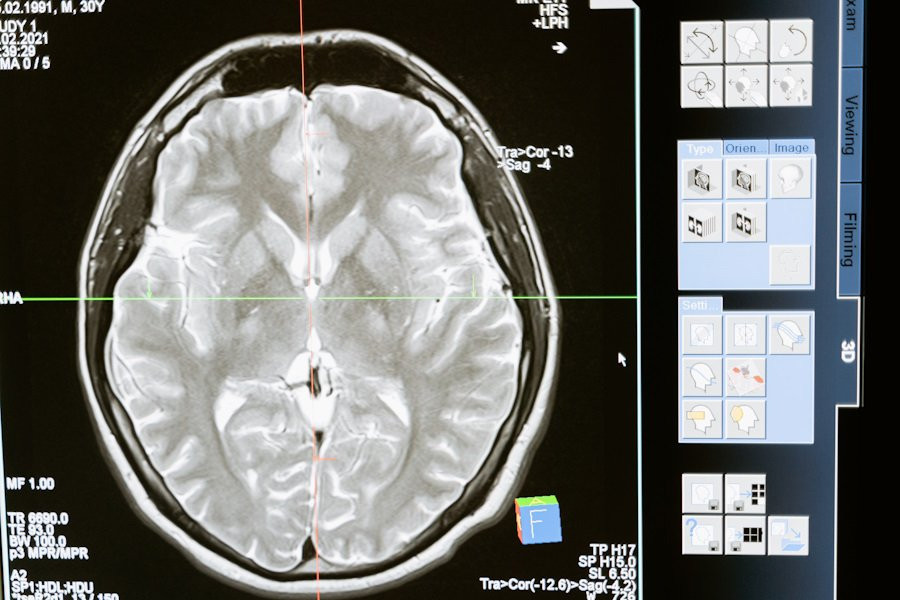

Фото из открытых источников

Нейробиологи из Northwestern University в США представили свои последние открытия, которые существенно изменяют наше понимание о том, как воспаление мозга воздействует на память. Согласно порталу Nature, исследование показывает, что воспаление нейронов головного мозга и повреждение ДНК могут играть положительную роль в формировании долговременных воспоминаний.

Ранее считалось, что воспаление нейронов может быть связано с риском развития болезней, таких как Альцгеймер и Паркинсон. Однако, новые исследования показывают, что воспалительные процессы в области гиппокампа, важного центра для обработки информации о прошлых событиях, необходимы для создания воспоминаний.